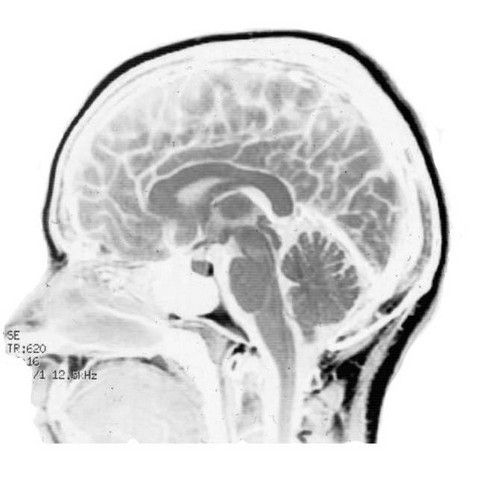

Neurología de la música y del lenguaje